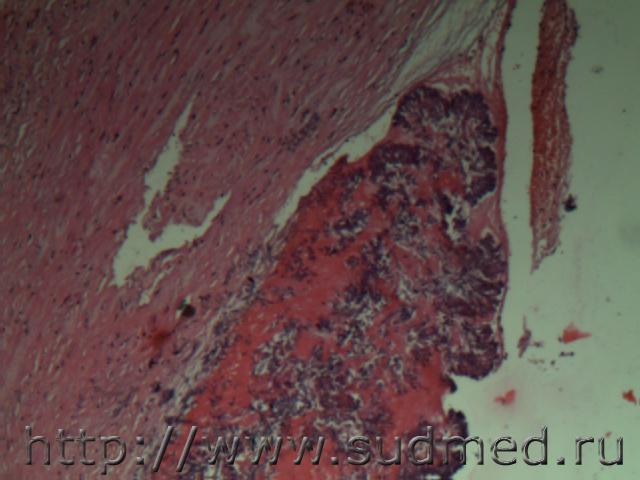

Ув.коллеги! Демонстрирую Вам микрофото инфаркта миокарда с лейкоцитарной демаркационной зоной.